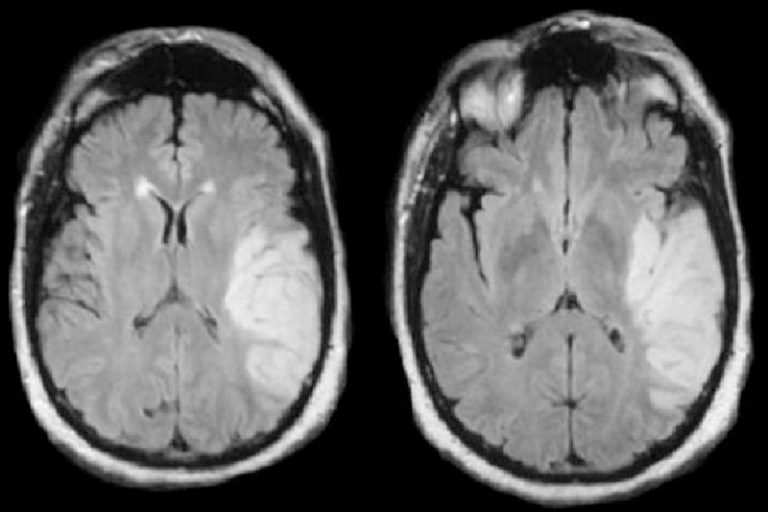

患有缺血性中風病者的磁力共震圖片。